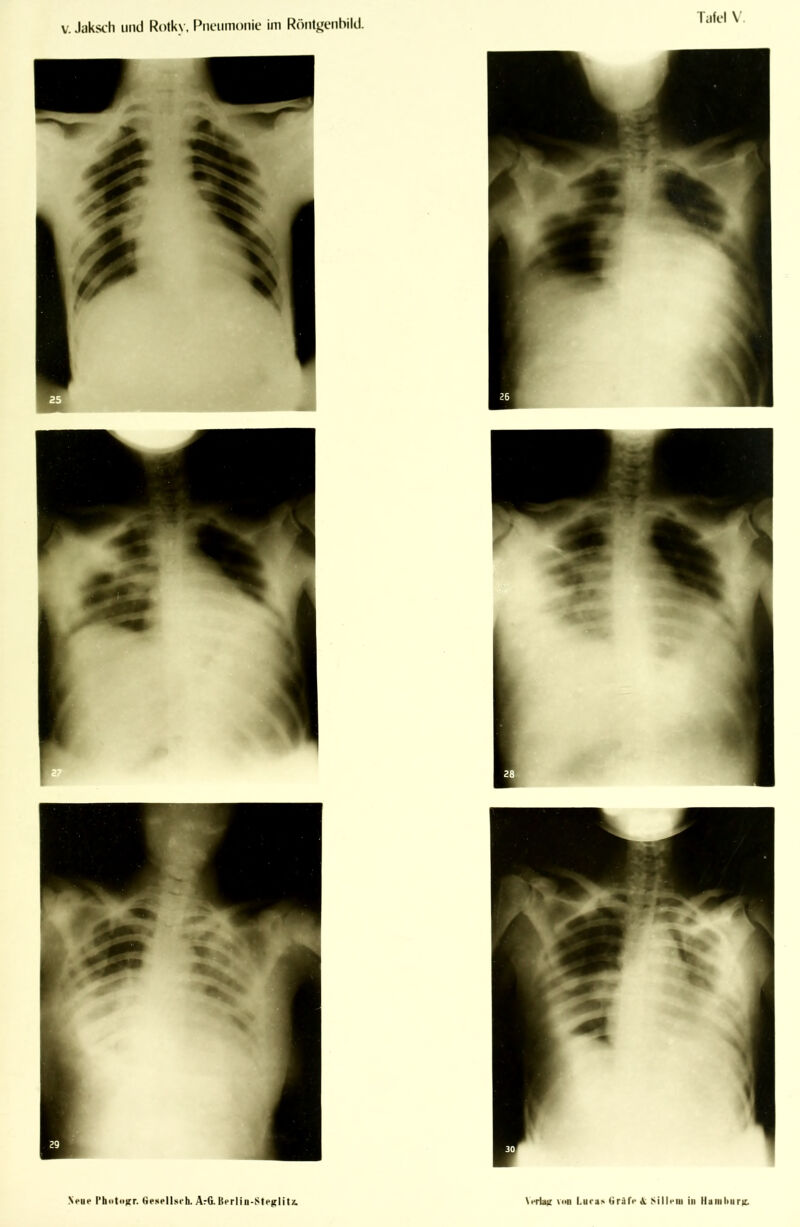

Die Pneumonie im Röntgenbilde ... : mit 59 Röntgenbildern auf 10 Tafeln und 10 Skizzenblättern / von R.v. Jaksch und H. Rotky.

Credit: Die Pneumonie im Röntgenbilde ... : mit 59 Röntgenbildern auf 10 Tafeln und 10 Skizzenblättern / von R.v. Jaksch und H. Rotky. Source: Wellcome Collection.